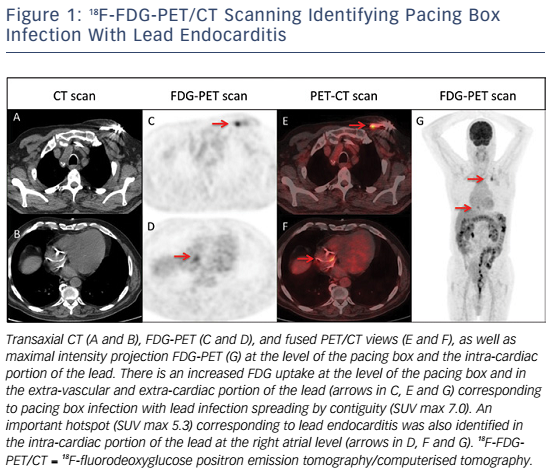

Figure 1 18F FDG PET CT Scanning Identifying Pacing Box Infection With